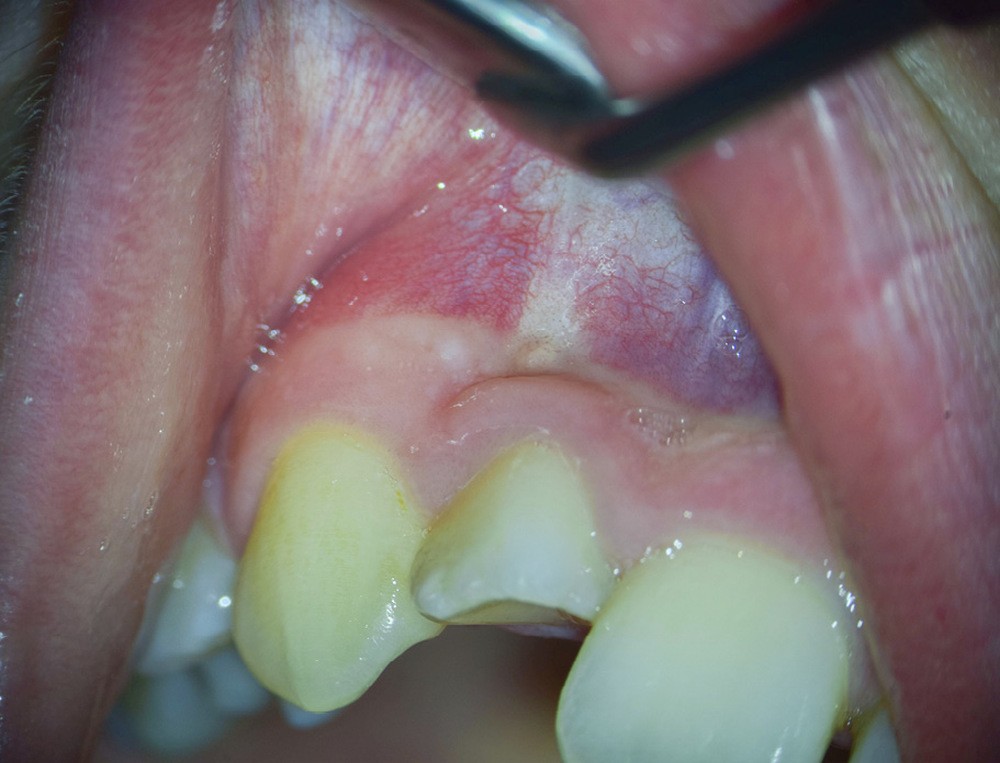

La patiente, âgée de 12 ans, s’est présentée à ma consultation avec une demande du chirurgien de réaliser le traitement endodontique de la 12 avant le curetage sous anesthésie générale. La radiographie périapicale préopératoire a mis en évidence une anatomie complexe. Les tests préopératoires ont montré un sondage parodontal sain, une percussion positive et un test au froid positif. La patiente présentait également une fistule vestibulaire active. Le Cone Beam a mis en évidence la présence d’une dens in dente et d’une lésion imposante ainsi qu’une palatoversion importante de la racine de la 12. La lésion est-elle responsable de ce mouvement dentaire ? (fig. 1, 2 et 3).

Lors du traitement endodontique, un suintement important étant encore présent à la fin de la seconde séance. J’ai pris la décision d’irriguer la crypte osseuse et sa lésion à travers la fistule à l’aide d’iso-bétadine délivrée par une aiguille stérile. C’est par empirisme que je réalise cette manœuvre ayant déjà montré à chaque reprise des résultats cliniques positifs. C’est l’équivalent d’une décompression sans tous les désavantages de cette dernière (fig. 4 et 5).